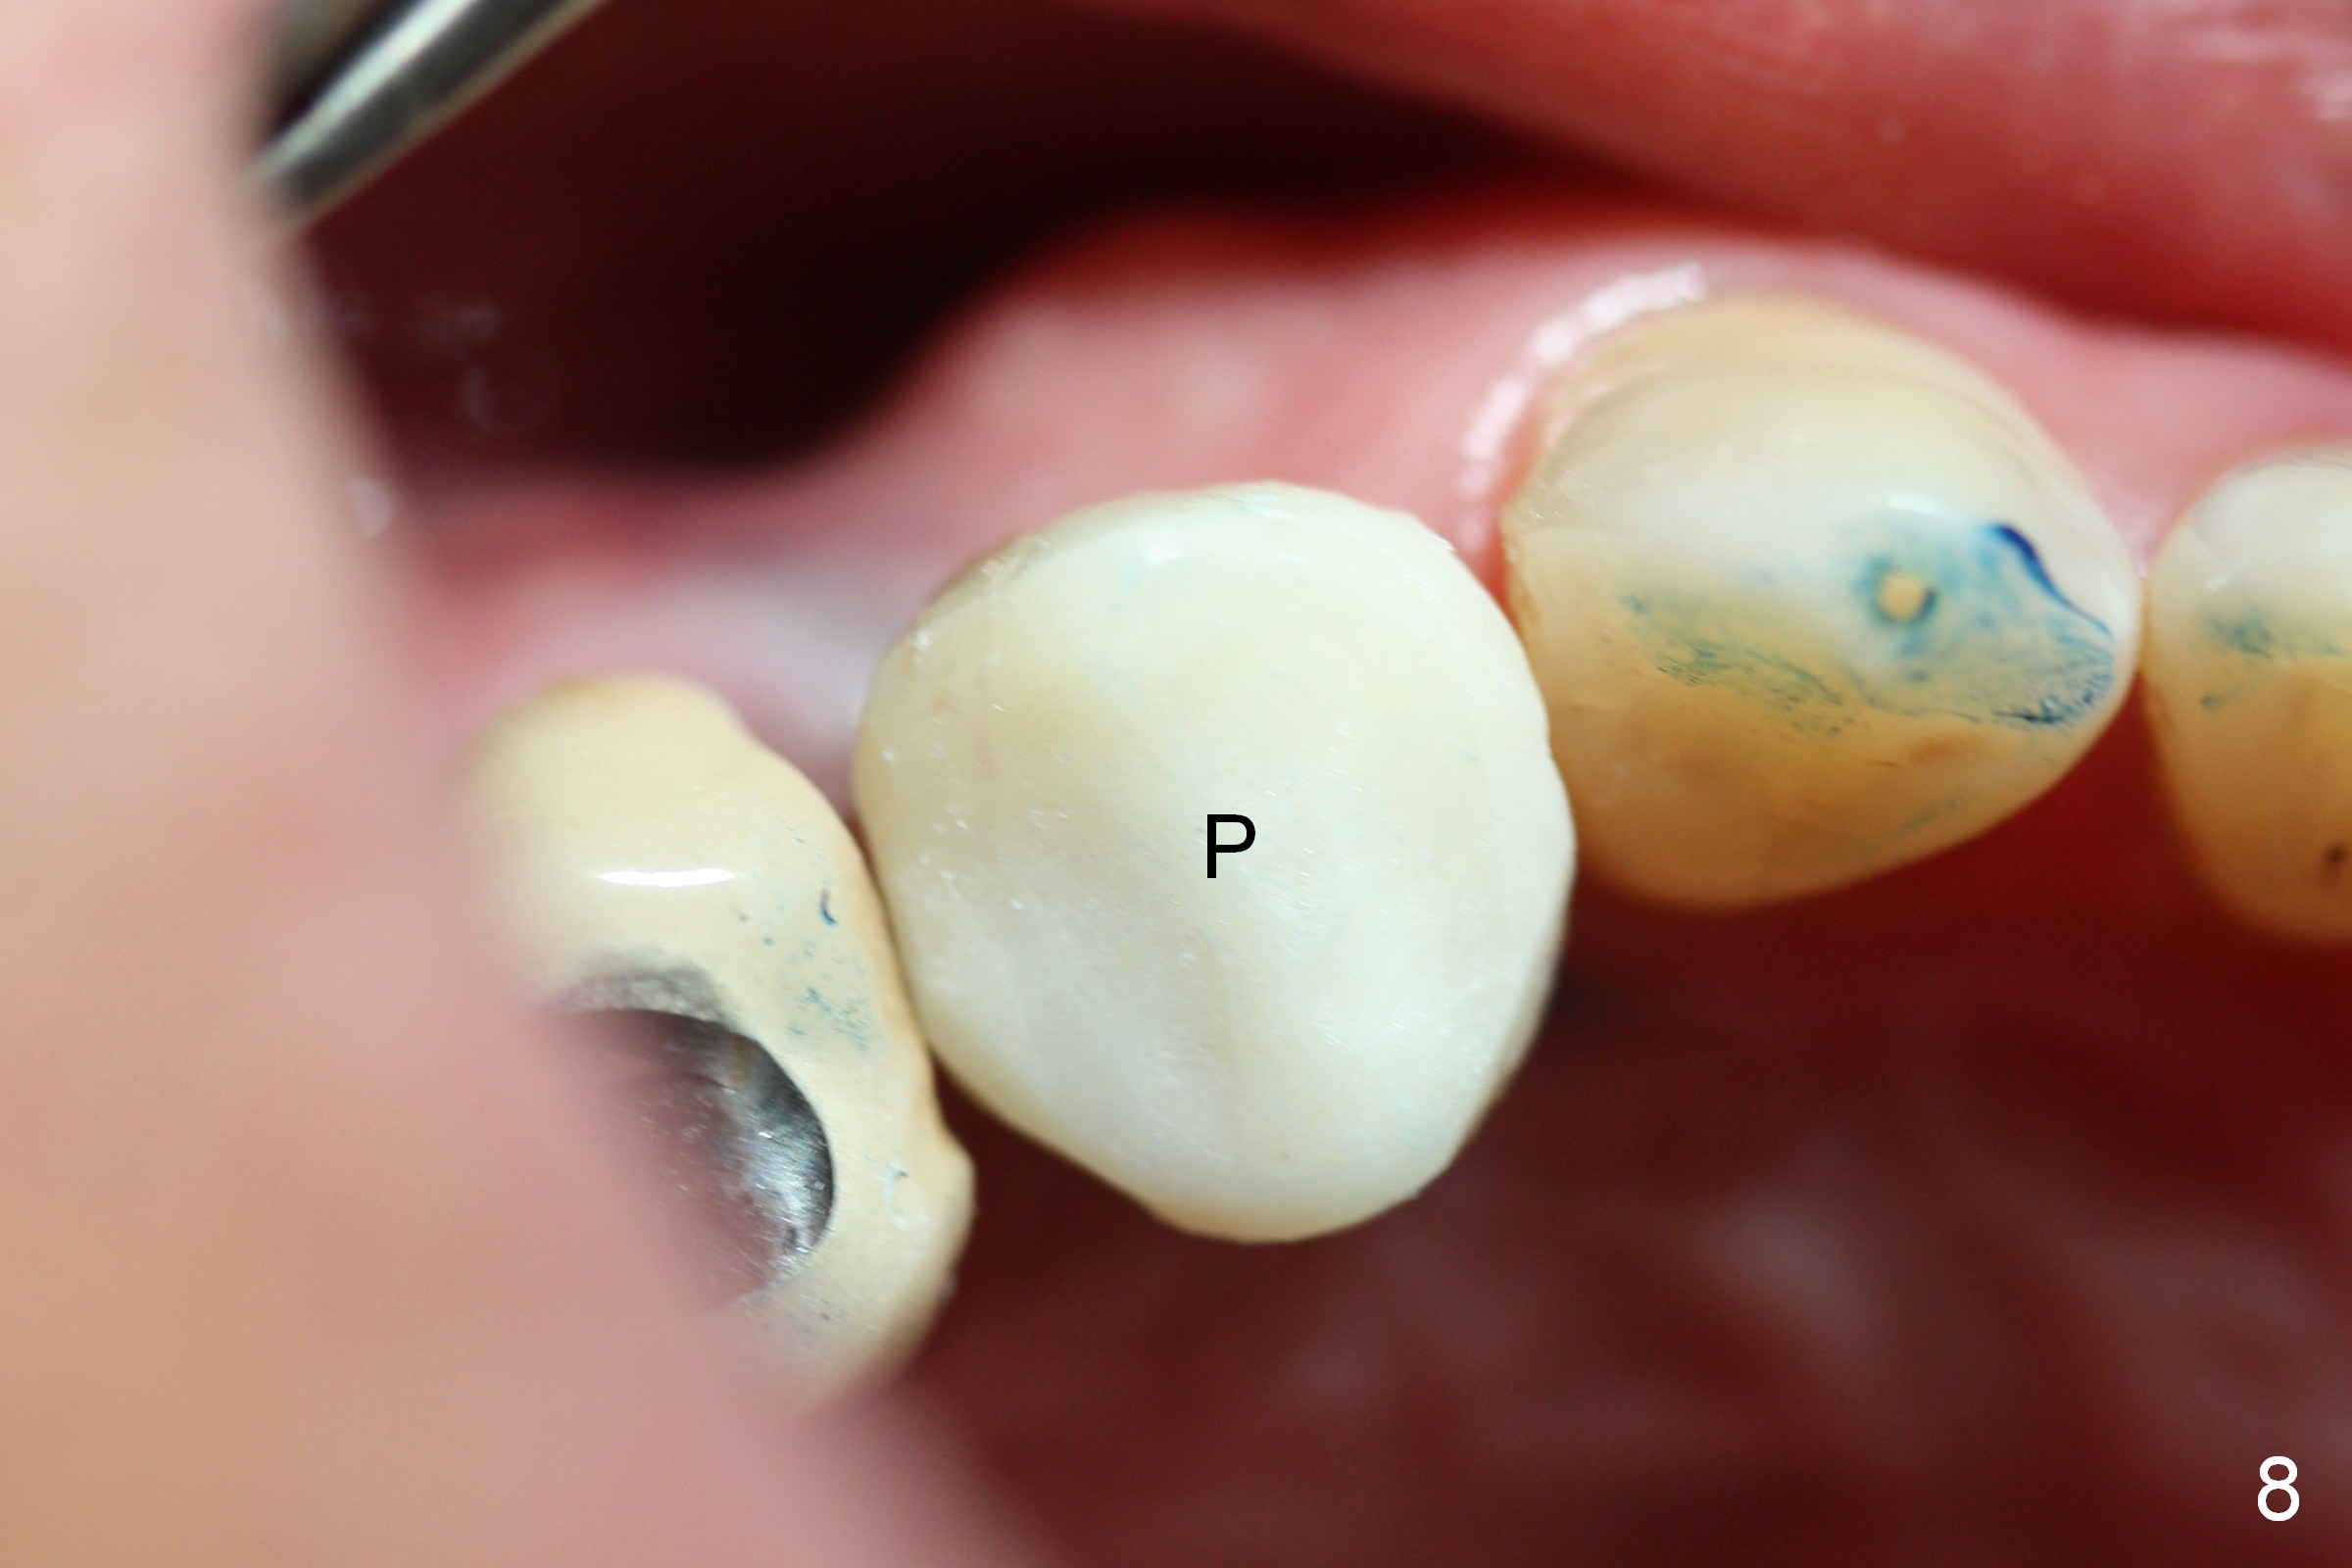

A 66-year-old man has lost several teeth (Fig.1,2). There is a particularly wide mesiodistal space for the site of #5 (Fig.1), probably due to distalization of the tooth #4 under heavy occlusion (Fig.2 arrow). A 4 mm tissue punch is used for access, followed by 1.6 mm pilot drill (Fig.3). After trajectory adjustment, a 2 mm parallel pin is inserted (Fig.4); later the osteotomy is moved distally (arrow). Finally a 4.5x14 mm implant is placed (Fig.5 I). Due to limited access, the implant is placed a little deeper than necessary; the gingival cuff of an abutment has to be longer (Fig.6 A: 5.8x4(3) mm). An immediate provisional is fabricated (Fig.7,8 P). The provisional looks wide (Fig.7). When the implant osteointegrates, limited orthodontic treatment will be done to idealize the space of #5 as follows.

The distal surface of the provisional will be reduced (Fig.9,10 D), whereas the occlusal surface will be increased (Fig.9 O). If needed, the occlusal surface of the distalized tooth #4 will be reduced (Fig.9 red area) so that there is no interference for tooth to move. Hooks will be placed on the buccal and lingual surfaces of the provisional (Fig.10 green curved lines). Power chains will be placed on the hooks and wrapped around the tooth #4. In due time, the tooth will be mesialized (Fig.11 arrow). Implants at the sites of #2 and 3 will be placed in more appropriate positions.